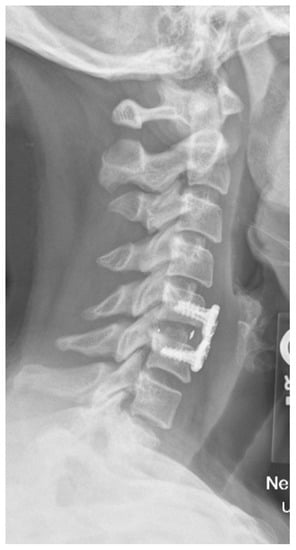

- Amelot, A.; Colman, M.; Loret, J.-E. Vertebral body replacement using patient-specific three–dimensional-printed polymer implants in cervical spondylotic myelopathy: An encouraging preliminary report. Spine J. 2018, 18, 892–899. [Google Scholar] [CrossRef] [PubMed]

- Phan, K.; Sgro, A.; Maharaj, M.M.; D’Urso, P.; Mobbs, R.J. Application of a 3D custom printed patient specific spinal implant for C1/2 arthrodesis. J. Spine Surg. 2016, 2, 314. [Google Scholar] [CrossRef] [PubMed] [Green Version]